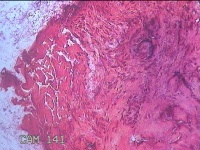

右侧食指指间关节内侧皮下结节

发现右侧食指指间关节内侧皮下结节1年余,无明显疼痛及不适。

大体所见

灰白暗红色带皮肤样结节0.8x0.5x0.2cm一个,表面糜烂,切开结节呈实性,切面灰白粉红色,质硬。